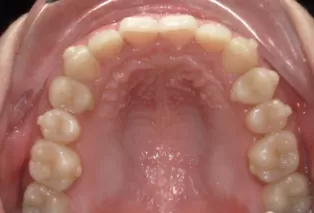

Photos intra-orales après traitement